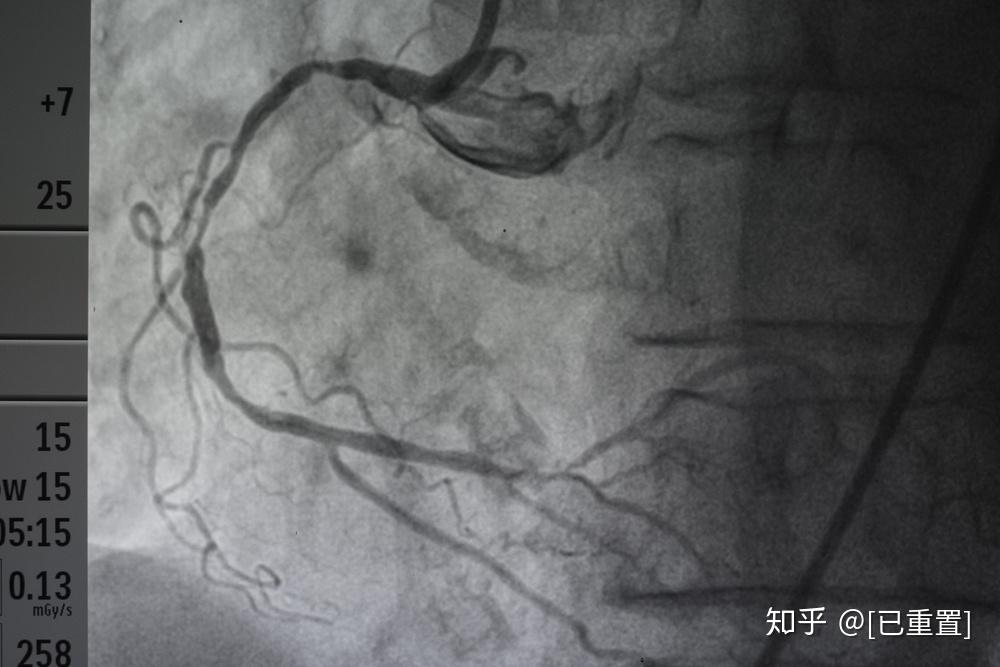

冠脉造影提示:左冠状动脉的前降支也有重度狭窄

清晰的心脏冠脉造影图片!

有图有真相,大家关心的急诊冠状动脉造影和介入治疗来啦!